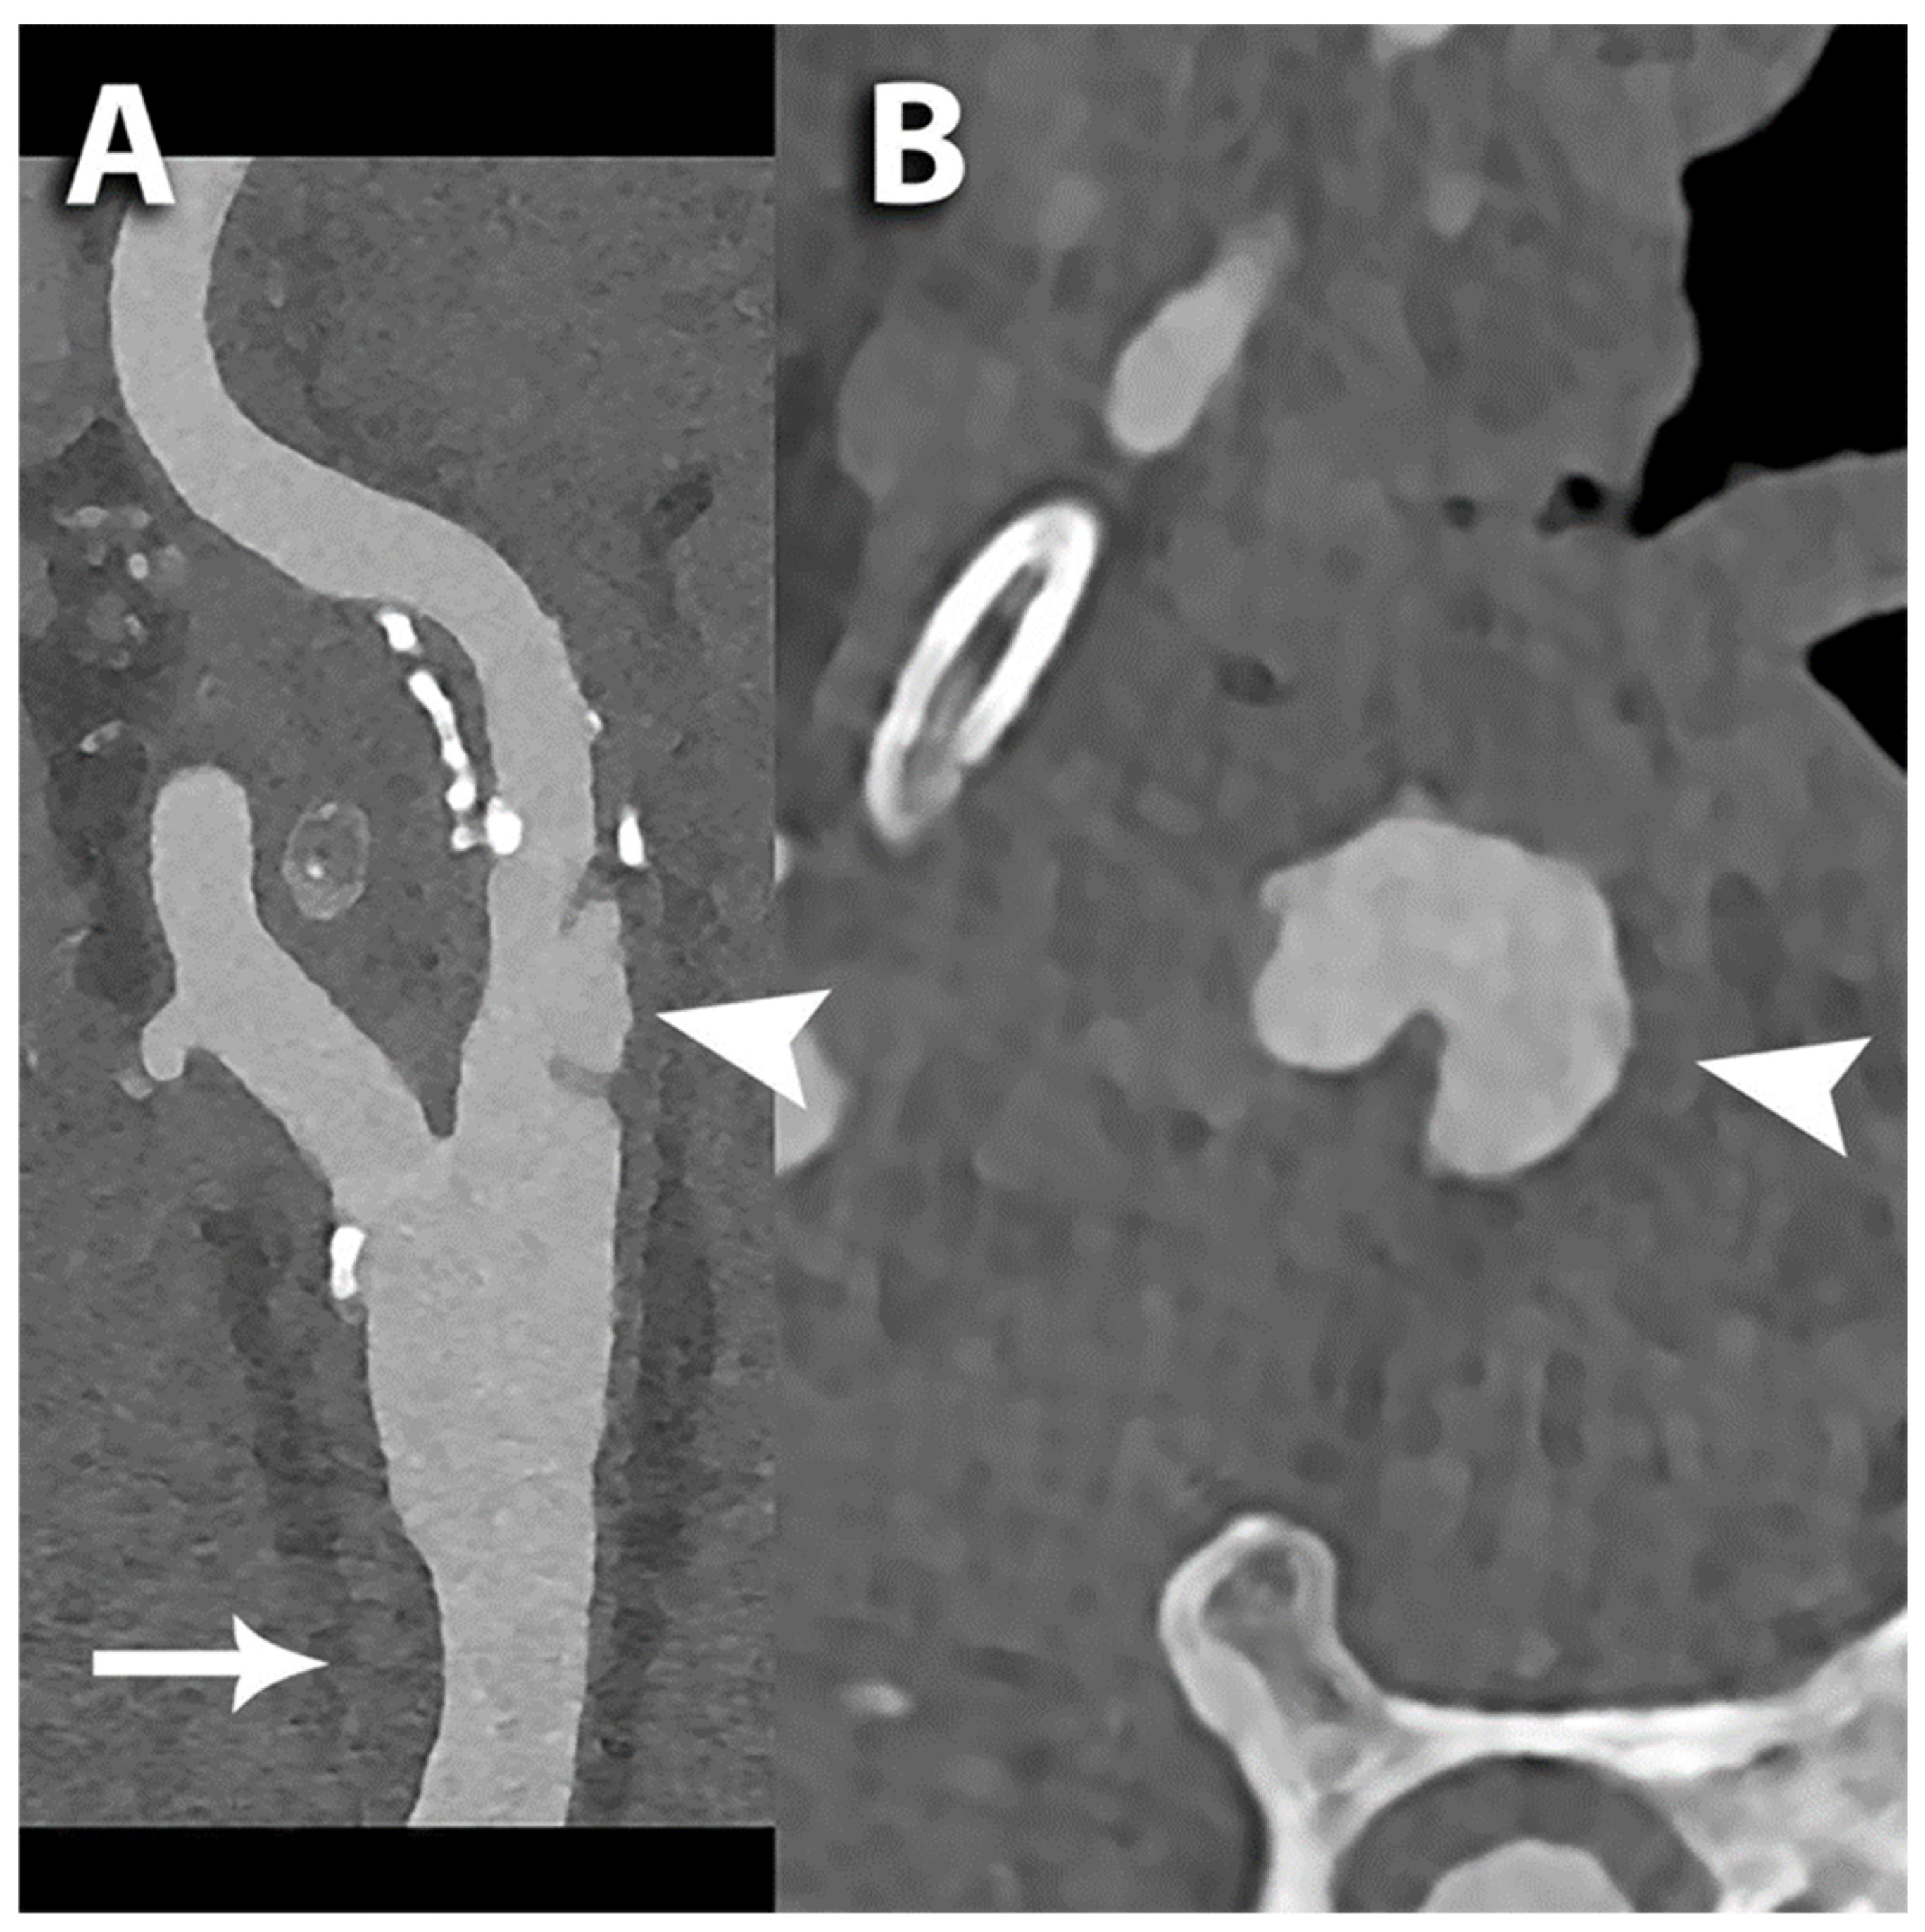

6.1. Carotid Lumen Evaluation

6.3. Carotid Plaque Evaluation

6.4. Proliferation of Vasa Vasorum